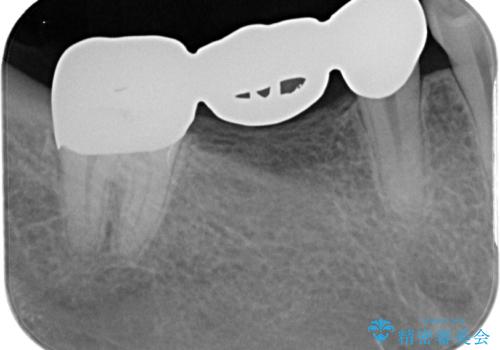

金属ブリッジを除去し、虫歯を完全に除去し、形を整え、

精度の高いシリコーン材料にて型どりをしました。

精度の高いブリッジなので、しみるなどの症状もなく経過も良好です。